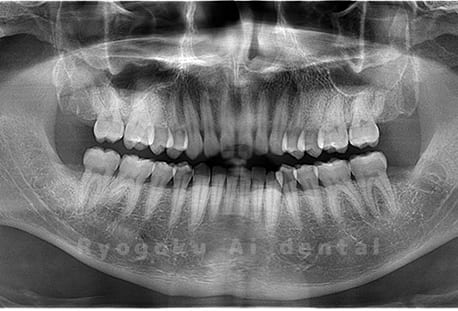

真っ直ぐ生えている親知らず

親知らずが真っ直ぐ生えているタイプです。

このタイプは真っ直ぐ生えていて咬み合わせに問題がなければ、抜歯しないケースもあります。ただし、虫歯になっていたり、痛みがあったり、咬み合わせが悪かったりすると抜歯をおすすめします。